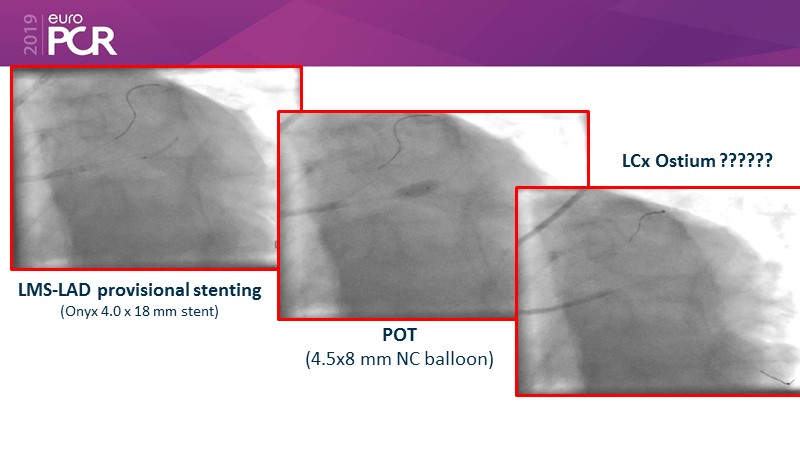

- To discuss contemporary treatment strategies for LMCA bifurcation lesions and to reflect on practical cases